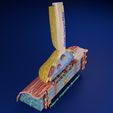

神经肌肉接头示意图